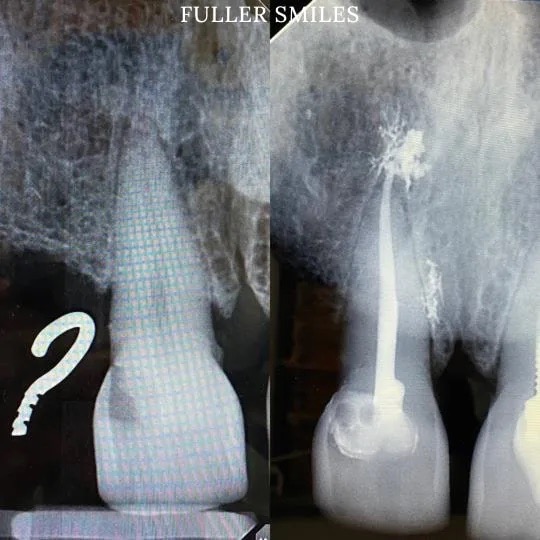

Patient presented with a complaint of severe constant pain that would exaggerate on laying down and biting. A thorough clinical exam, endodontic screening and proper x rays led to the diagnosis of necrotic pulpal tissue(dead pulp tissue) due to secondary dental caries with inflamed periodontal ligaments.

The tooth also had periapical abscess(infection at the bottom of the tooth). Our Dentists used the latest technology and highest quality products to disinfect the root canal system using medication to finish this beautiful root canal. The tooth was crowned after the root canal to restore function and aesthetics.